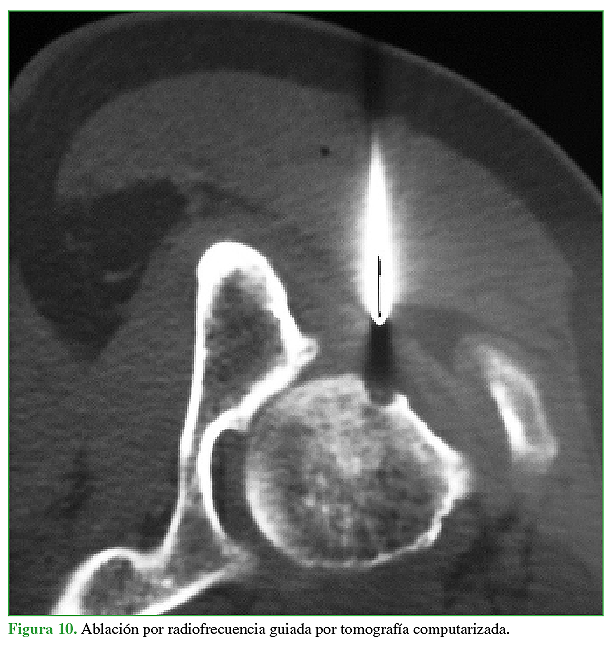

Acceso mediante suscripción PDF Acceso mediante suscripción PDF_EN (English) Acceso mediante suscripción Figura 1 Acceso mediante suscripción Figura 2 Acceso mediante suscripción Figura 3 Acceso mediante suscripción Figura 4 Acceso mediante suscripción Figura 5 Acceso mediante suscripción Figura 6 Acceso mediante suscripción HTML